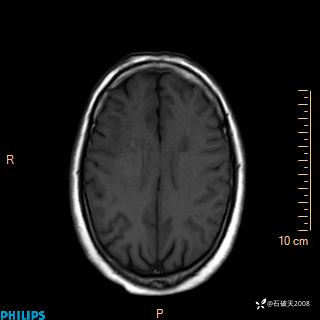

2020.11.14MR

T1